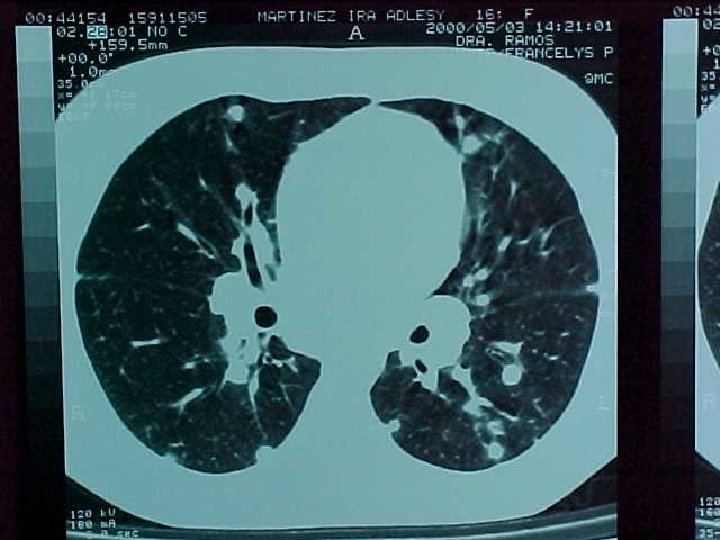

Histoplasmosis asociada a cueva en Venezuela Resultados: 28 estudiantes (17 hembras y 11 varones; rango de edad entre 15 -18 años con una media de 17 años) *20 (71. 4%) desarrollaron enfermedad aguda -64. 3% dentro de los 10 -28 días (mediana 14 días) posterior a la exposición. *2 (7. 1%) asintomáticos, tuvieron alteraciones radiológicas y en la serología para histoplasmosis.

Histoplasmosis asociada a cueva en Venezuela Resultados: 20 estudiantes enfermos-síntomas *Fiebre (77. 7%) *Dolor abdominal (38. 8%) *Tos no productiva (72. 2%) *Astenia (33. 3%) *Cefalea (66. 6%) *Dolor torácico (22. 2%) *Nauseas y vómitos (50%) *Disnea (16. 6%) *Rash (38. 8%) *Mialgias (16. 6%) *Eritema Nodoso (5. 5%)

Histoplasmosis asociada a cueva en Venezuela Conclusiones 1. -Aunque la cueva no es ambientalmente favorable para la transmisión de Histoplasmosis, por su elevada humedad interna predominante durante gran parte del año, el gran porcentaje de personas del grupo estudiado que desarrolló infección y enfermedad clínica en relación con una exposición ambiental relativamente breve, es indicativo de la ocurrencia de un elevado inóculo 2. -Este reporte constituye el más grande de los registrados en la literatura mundial